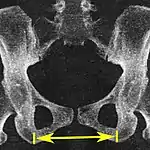

| Interspinous distance | ![]() |

The line between the closest bone points of the ischial spines | 9.5 to 11.5 cm.[6] | |